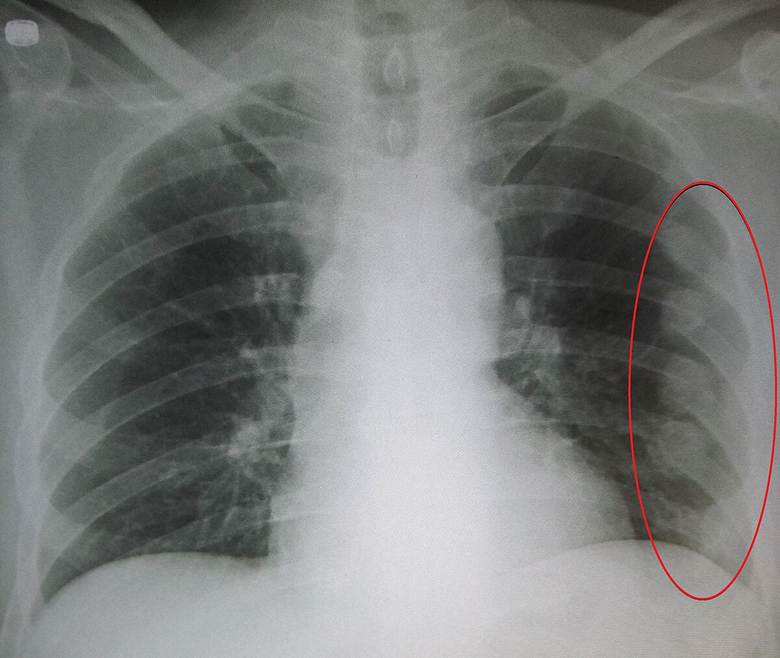

1. Chest X-ray

- Confirms fracture

- Detects pneumothorax